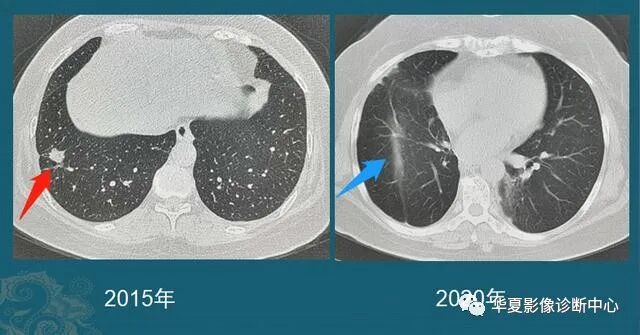

从1个小结节,发展成肺癌,需要几年?看看诊断实例...